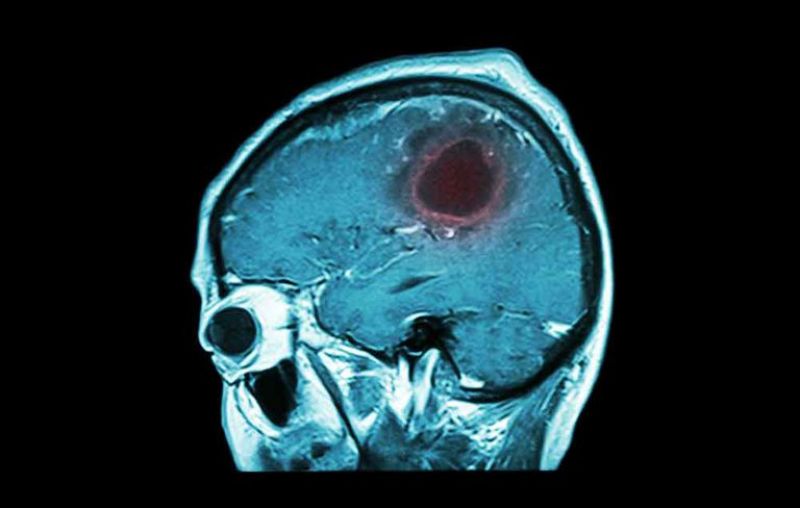

ਤੁਸੀਂ ਅਪਣੇ ਆਲੇ ਦੁਆਲੇ ਕੁੱਝ ਅਜਿਹੇ ਲੋਕਾਂ ਨੂੰ ਜ਼ਰੂਰ ਦੇਖਿਆ ਹੋਵੇਗਾ, ਜਿਨ੍ਹਾਂ ਨੂੰ ਅਕਸਰ ਸਿਰ ਵਿਚ ਭਾਰਾਪਣ ਅਤੇ ਬੰਦ ਨੱਕ ਦੀ ਵਜ੍ਹਾ ਨਾਲ ਸਾਹ ਲੈਣ ਵਿਚ ਤਕਲੀਫ਼ ਦੀ ਸ਼ਿਕਾਇਤ ਹੁੰਦੀ ਹੈ। ਦਰਅਸਲ ਅਜਿਹੇ ਲੋਕ ਸਾਈਨੋਸਾਇਟਿਸ ਯਾਨੀ ਸਾਇਨਸ ਦੀ ਸਮੱਸਿਆ ਤੋਂ ਪੀਡ਼ਤ ਹੁੰਦੇ ਹਨ। ਆਉ ਇਸ ਰੋਗ ਦੇ ਬਾਰੇ ਵਿਸਥਾਰ ਨਾਲ ਜਾਣਦੇ ਹਾਂ। ਬ੍ਰੇਨ ਟਿਊਮਰ ਦਿਮਾਗ ਵਿੱ ਗ਼ੈਰ-ਅਸਧਾਰਨ ਕੋਸ਼ਿਕਾਵਾਂ ਦਾ ਇਕ ਸਮੂਹ ਹੈ।

ਖੋਪੜੀ ਦੇ ਅੰਦਰ ਗ਼ੈਰ-ਅਸਧਾਰਨ ਕੋਸ਼ਿਕਾਵਾਂ ਦੇ ਵਾਧਣ ਦੀ ਸਮੱਸਿਆ ਪੈਦਾ ਕਰ ਸਕਦੀ ਹੈ। ਬ੍ਰੇਨ ਟਿਊਮਰ ਕੈਂਸਰਜੰਨਿ( ਮੈਲਿਗਨੇਂਟ) ਜਾਂ ਕੈਂਸਰ ਰਹਿਤ (ਬਿਨਾਇਨ) ਹੋ ਸਕਦਾ ਹੈ। ਜਦੋਂ ਮੈਲਿਗਨੇਂਟ ਟਿਊਮਰ ਵਧਦੇ ਹਨ ਤਾਂ ਉਹ ਤੁਹਾਡੀ ਖੋਪੜੀ ਦੇ ਅੰਦਰ ਦਬਾਅ ਵਧਾ ਸਕਦੇ ਹਨ, ਇਹ ਦਿਮਾਗ ਨੂੰ ਨੁਕਸਾਨ ਪੁਹੰਚਾਉਣ ਦੇ ਨਾਲ ਨਾਲ ਜੀਵਨ ਨੂੰ ਵੀ ਖਤਰੇ ਵਿਚ ਪਾ ਸਕਦੇ ਹਨ। ਬ੍ਰੇਨ ਟਿਊਮਰ ਮਰਦ ਅਤੇ ਔਰਤਾਂ ਦੋਹਾਂ ਵਿਚ ਹੋ ਸਕਦਾ ਹੈ।